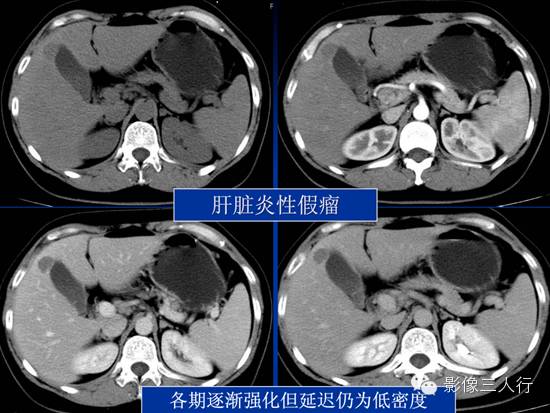

CT平扫:表现肝脏实质内可见孤立或散在的低密度影,直径约小于3.0cm,其形态多样,以类圆形多见,病灶边缘清晰或模糊; 动脉期:炎性假瘤多无直接的动脉供血,所以动脉期多强化不明显; 门脉期及延迟期:①病灶不均匀强化,周边环形强化(表明病灶中心血管较少,中心以凝固性坏死,炎性细胞浸润为主);②病灶均匀强化(表明病灶内血供丰富,大量炎性细胞浸润和纤维组织相互夹杂);③病灶无强化(表明病灶内血管无或较少,以大量凝固性坏死为主,多伴少量的炎性细胞浸润)。 |

病例二肝脏炎性假瘤CT表现:平扫,肝内见不规则的低密度区,边缘不清,形态似片状或葫芦形;动脉期病灶内部未见明显强化;门脉期,边缘及分隔有中度强化;延迟期,病灶强化范围进一步扩大,与肝脏实质密度基本一致。